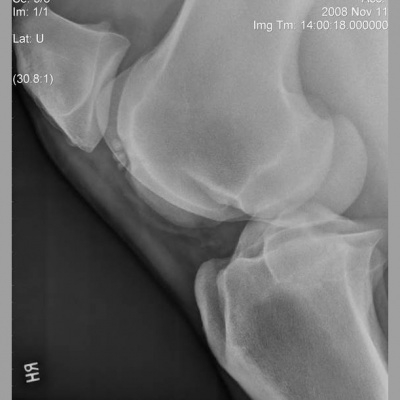

This week David chats to Huw and Lucy about health and safety in relation to radiographs and discusses BEVA's latest initiative which aims to help tackle equine obesity.